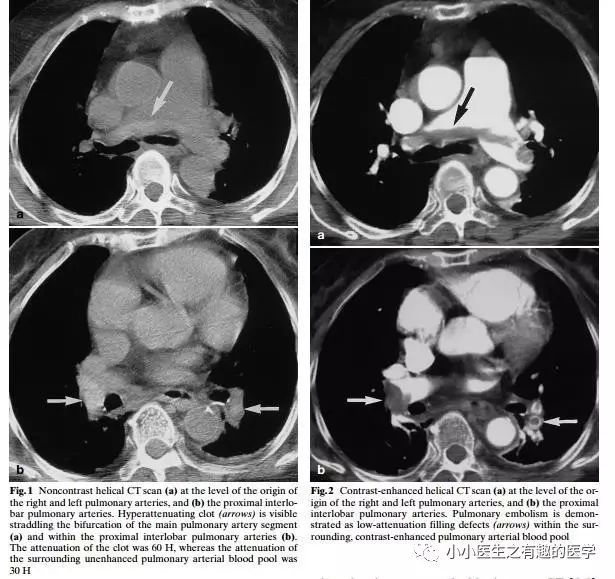

如图,高密度影的那一条。

不怕,有增强CT证实。

上面图片的英文原版

1.Gotway M B, Webb W R. Acute pulmonary embolism: visualization of high attenuation clot in the pulmonary artery on noncontrast helical chest CT[J]. Emergency Radiology, 2000, 7(2):117-119.